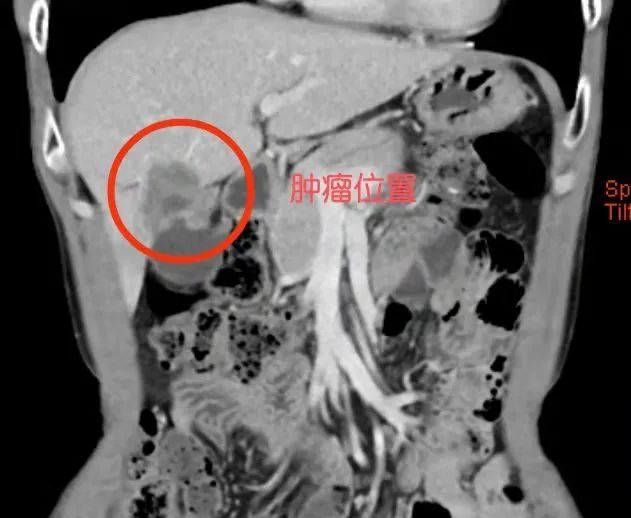

据悉,43岁的黄先生因在县级医院检查发现“肝占位十余天”,后因当地条件有限遂转至我院肝胆外科进一步治疗,经详细检查发现肝脏有一4cmX4cm×3cm大小的肿瘤,且肿瘤呈进行性增大,若不及时手术,会加大自发性或外伤性破裂出血的风险。

患者术前肝肿瘤CT情况